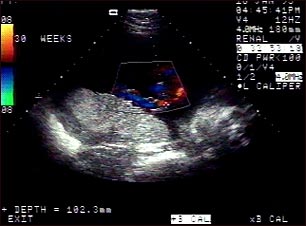

Ultrasonido normal a color -l cordón umbilical

Ultrasonido Doppler normal a color, del cordón umbilical, a las 30 semanas de gestación. El cordón corresponde al área coloreada en el centro de la pantalla y los vasos del mismo están representados por diferentes colores. El cordón umbilical normalmente se compone de tres vasos sanguíneos, a saber, dos arterias y una vena y está conectado a la placenta, la cual está ubicada en la parte central izquierda de la imagen.